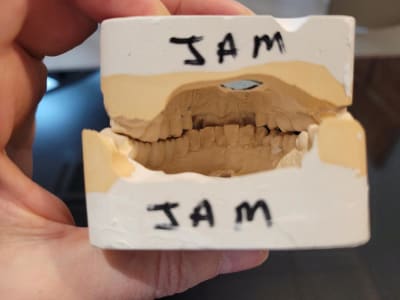

je reçois cette patiente de 70 ans pour une fracture de la 28. Je l'avais vu en 2016 pour une réfection de son bridge secteur 3. Quand je lui demande de serrer voici ce que je trouve. Je ne comprends pas bien ce qu'il s'est passé... Quand je l'interroge, elle me dit qu'elle éprouve des difficultés à la mastication depuis 3 mois avec problèmes de morsure à gauche. Au début je pensais qu'avec extraction des DS et réfections des couronnes sur les 7 a droite cela pourrait passer mais les prémo su se sont versées en palatin. Bref je mouline !

ce que tu nous montres là , c est la position de fermeture telle que tu l as vu au fauteuil ? je suppose .

alors , fais des reperes sur les platres dans cette position puis ,

enlève les modeles de l articu et essayes de trouver une autre occlusion stable possible en les tenant à la main . tu devrais y trouver l occlusion d intercuspidie d avant le pb articulaire .

et tu regardes le trajet d une position à l autre .

l ideal ce serait que tu nous envoies la photo des 2 modeles posés les un sur les autres en oim en mettant en evidence la difference traits reperes de ton montage sur articu et de l oim ant possible .

Je fais suite avec l'OIM que je trouve. a priori, Déviation a gauche. Serait ce pour repositionner L'atm droite ou pour éviter une gêne a droite ? (en rouge rapport sur articu )